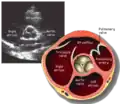

Parasternal short axis (PSAX)

Parasternal short axis at mid-LV showing papillary muscles

Parasternal short axis showing aortic valve

This view is obtained in the same window as the parasternal long, but with the probe rotated 90°. In this view, the aortic valve is seen in cross-section with the right ventricular inflow & outflow tracts visible with the tricuspid valve as well. Pulmonary valve is not visible in this view. Both the right and left atria are visible.

The standard PSAX view is at the level of the aortic valve, but moving the probe along the long-axis can review the LV outflow tract, LV at the base, and LV at the midsection.

Structures visible:

• Aortic valve in short-axis

• Aortic valve dysfunction, aortic sclerosis/stenosis

• Tricuspid valve in long-axis

• Pulmonary valve in long-axis

• Right ventricle, including inflow and outflow tracts

• Left ventricle in short-axis

• Closer to the base can reveal the left ventricular outflow tract

• At the level of the base can show the movement of the mitral valve leaflets in short-axis

• At the level of mid-LV can show papillary muscles